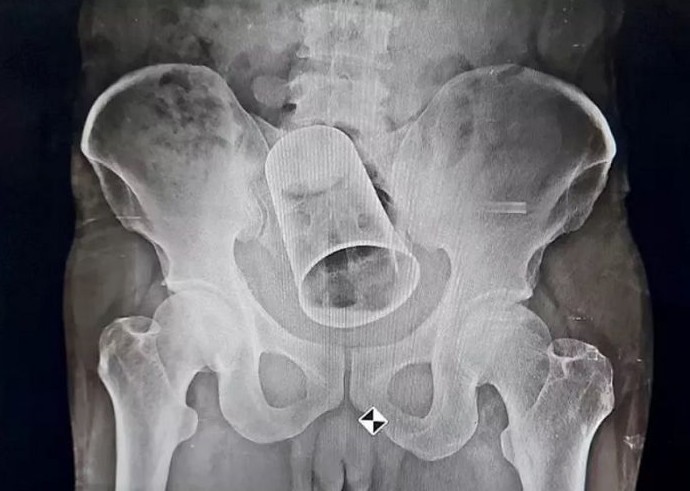

Несколько дней назад ему хирургическим путем из его прямой кишки извлекли металлический стаканчик приличного размера: около 8 сантиметров в диаметре и 15 сантиметров в длину.

После госпитализации пострадавшему сделали рентген и поняли причину вздутия живота. Мужчина не испражнялся с момента самого "розыгрыша". Сначала хирурги пробовали извлечь объект руками и подручными средствами, но ничего не вышло.

Хирургическая операция продлилась два с половиной часа, но завершилась успешно. Здоровью мужчины больше ничего не угрожает.